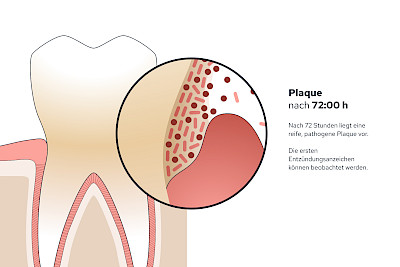

Plaque (Biofilm)

Als Plaque bzw. Biofilm bezeichnet man die Gesamtheit aller Mikroorganismen (Mikrobiom) auf der Zahnoberfläche. Werden die Zähne nicht geputzt, haften die Beläge nach 24 Stunden bereits so fest, dass diese mit der Zahnbürste schon nicht mehr vollständig entfernt werden können.

Im Anfangsstadium kann Plaque (Biofilm) durch Optimierung und Intensivierung der Mundhygiene (Zähneputzen mit Zahnpasta) noch reduziert werden. Lassen sich die Beläge mit Zahnbürste und Zahnpasta nicht mehr entfernen, muss der Zahnarzt unterstützen.